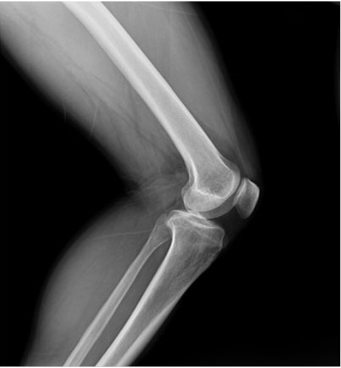

頸部片子